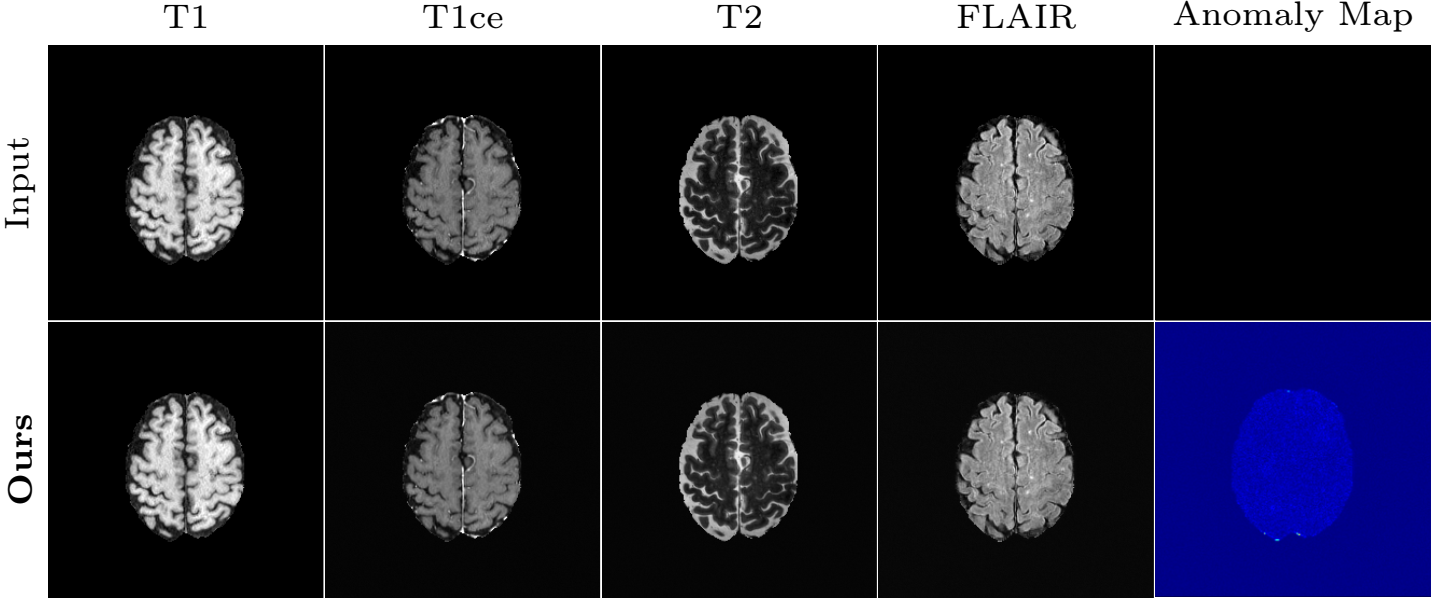

Translation of a healthy subject:

Expected result: our method makes no change to the healthy image.

Figure 16. Results of the proposed method on a slice without tumor of the BRATS dataset.

Observations:

The final anomaly map is almost invisible.

→ There is almost no difference between input and the synthetic image.

→ The reconstruction preserves almost all details.